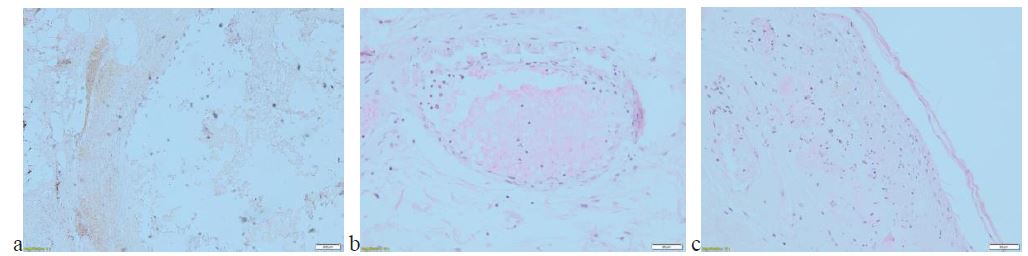

Figure 3: Histological features: (a) Calcification within adipose tissue and necrosis, (b) Circumferential calcification, (c) Necrosis of the epidermis and microcalcification.

Histopathological examination revealed interstitial calcification, vascular ectasia in the middle dermis and calcifications in the wall of small vessels, without evidence for gangrenous pyoderma. Von Kossa staining provided further evidence in favor of CUA (Figure 3).